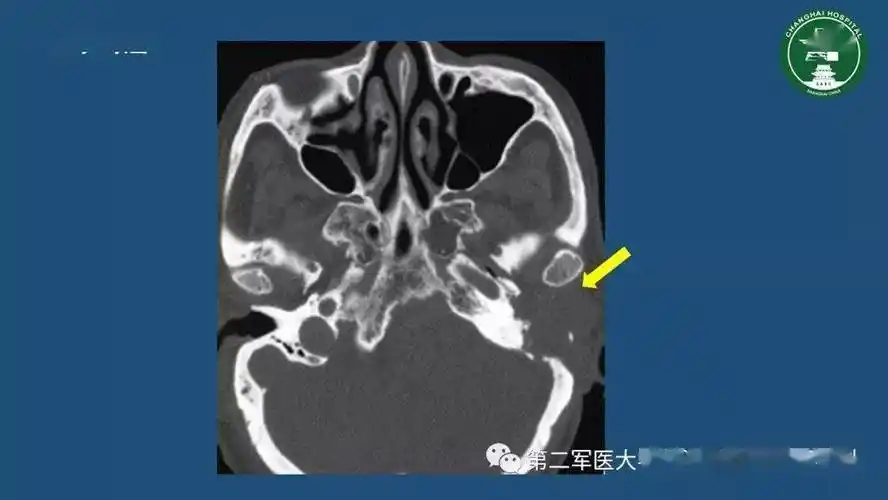

枕骨,颞骨有骨折吗

【求助】颞骨ct平扫

颞骨ct解剖及其常见病变